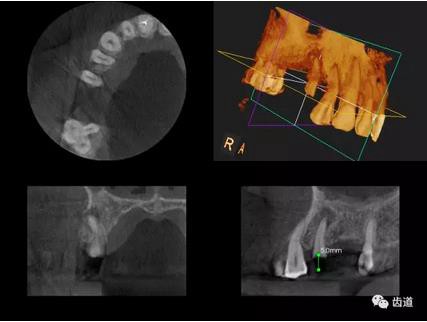

三)種植修復(fù)

CBCT在牙種植修復(fù)中的應(yīng)用。種植前利用CBCT對患者的牙床進行檢查,可精準(zhǔn)判斷牙槽骨的寬度、厚度及高度、骨的密度、重要的顏面神經(jīng)、血管和鼻竇位置等。臨床醫(yī)生不僅可以在計算機直觀的看到牙槽骨的立體影像,還可以切換不同的視角來觀察硬組織之間的位置關(guān)系,在手術(shù)方案中避開危險區(qū)域,保證手術(shù)的安全性。臨床醫(yī)生還可以利用CT數(shù)據(jù)進行數(shù)字模型重建,配合軟件預(yù)先做好手術(shù)模板,使種植手術(shù)更安全快捷,避免在種植手術(shù)過程中不慎破壞神經(jīng)、鼻竇等解剖結(jié)構(gòu),導(dǎo)致顏面神經(jīng)麻痹、鼻竇炎等并發(fā)癥的發(fā)生。

1、下頜骨種植牙前測量準(zhǔn)備影像

2、上頜骨種植牙前準(zhǔn)備影像

3、下頜骨種植牙術(shù)后